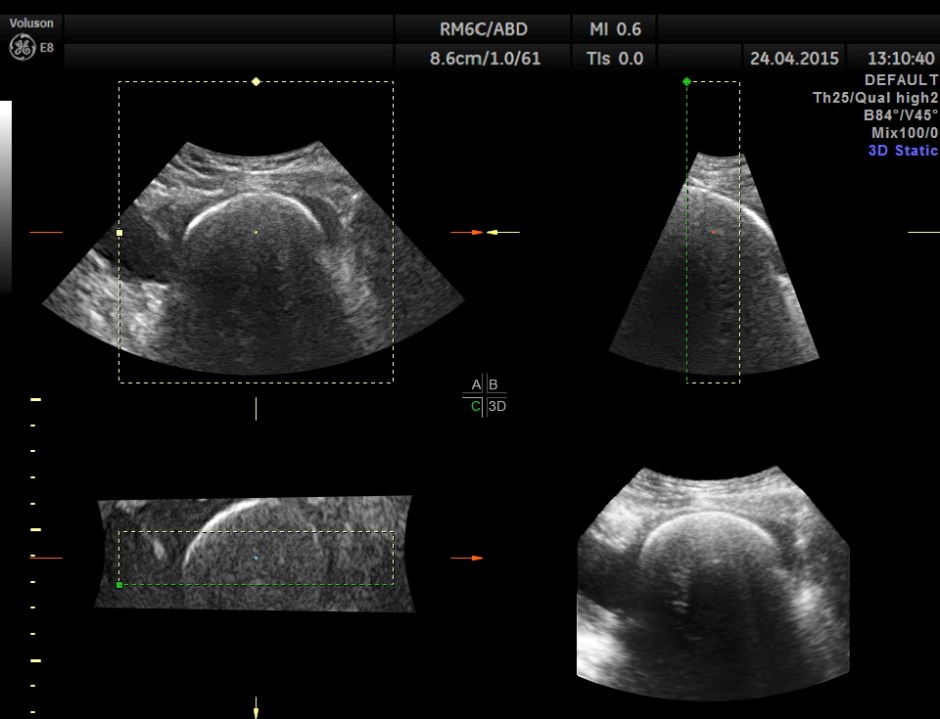

Scan of the urinary bladder in a more cephalic angle shows the following :

A large calcification in the urinary bladder – ? large urinary bladder stone , calcified median lobe of the prostate, or a calcified mass within the bladder .

3D tweaking looks more like a large stone.